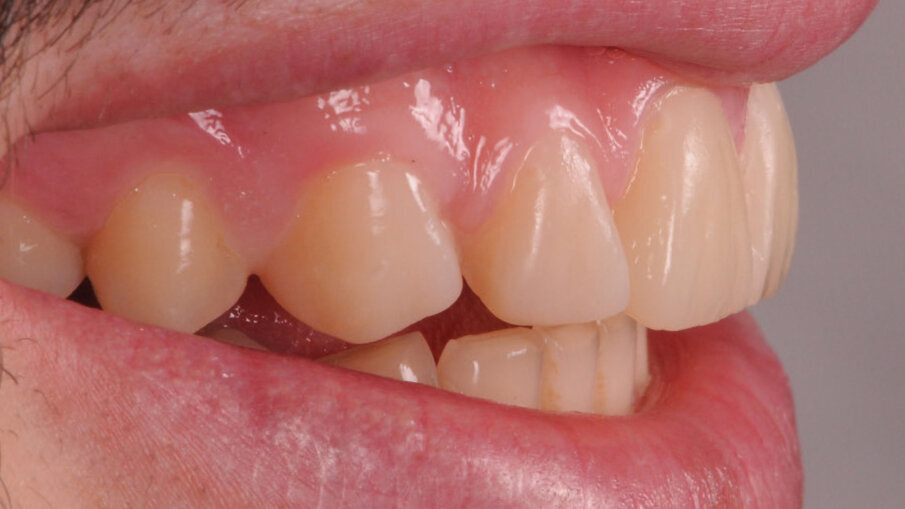

Paziente maschio di anni 26, si presenta alla prima visita con una esplicita richiesta di miglioramento estetico, in quanto non soddisfatto dei suoi denti e di conseguenza del suo sorriso. All’anamnesi riferisce di sorridere poco e con difficoltà, limitando la sua socialità1. Risulta fondamentale in questi casi la fase del colloquio iniziale, per far emergere gli aspetti che il paziente ritiene sgradevoli e cosa invece lo farebbe sentire a suo agio. Si utilizza la fase iconografica dimostrativa con fotografie eseguite su casi simili già finalizzati per mostrare al paziente le fasi cliniche e le possibili soluzioni alle sue richieste. Bisognerà dedicare molto tempo ad ascoltare il paziente, i suoi dubbi e le sue esigenze, capendo da subito le sue aspettative prima di impostare il piano di trattamento. L’esame clinico intraorale, mostra un’arcata superiore con microdonzia a carico degli incisivi laterali 12 e 22, con diastemi e volume ridotto degli elementi canini in proporzione alla dimensione ossea strutturale. Il termine microdonzia2 è spesso abusato, poiché non vi sono dei parametri che la letteratura indica per definire tale situazione, spesso gli elementi microdontici lo sono in rapporto agli altri elementi dentali come in questo caso. Gli elementi 11 e 21, originariamente normo formati, presentano irregolari abrasioni della superficie vestibolare probabilmente causate da tecniche di spazzolamento incongrue che hanno esposto delle isole di dentina vestibolare3 (Figg. 1-3).

Alterazioni dell’anatomia inoltre si evidenziano anche a livello dei margini incisali dove sono evidenti delle micro fratture a carico dello smalto, originate da un probabile sovraccarico occlusale. Andando alla ricerca di una possibile causa di questo tipo di alterazione morfologica, un’attenta analisi dei gruppi posteriori evidenzia anche qui una situazione inusuale, cioè un’evidente riduzione dello smalto della porzione occlusale degli elementi diatorici specificamente dei premolari e dei primi molari, con conseguente alterazione dell’anatomia, mentre un normale sviluppo e una normale conformazione occlusale degli ultimi molari 37 e 47. Completando la visita e concludendo l’analisi con il V sestante si nota una inevitabile abrasione a carico dello smalto degli incisivi inferiori con usura dei canini soprattutto sul lato destro dove il canino in posizione 43 risulta riportare un’abrasione molto importante a differenza del 33 che appare normo conformato (Fig. 4). Emerge quindi che la situazione intra orale mostra alcuni elementi con alterazioni congenite come gli incisivi laterali e altri elementi con alterazioni acquisite di natura erosiva-abrasiva. In entrambi i casi il percorso da seguire è quello di, studiare le forme dentali residue per “reintegrarle” basandosi sugli elementi integri, utilizzati come guida per una riabilitazione “anatomicamente” guidata.